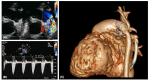

Hypoplastic left heart syndrome (HLHS) is a spectrum of left heart underdevelopment leaving the left side unable to support the systemic circulation. If active management is pursued, then the condition is managed with staged palliation to the Fontan circulation, leaving a systemic right ventricle. Through all surgical stages, and even after completion of Fontan, there are multiple areas that may require intervention, most frequently the branch pulmonary arteries which are essential to a successful Fontan circulation. Echocardiography is the mainstay of assessment, but there is an increasing use of magnetic resonance imaging (MRI) and computed tomography (CT) particularly in relation to extracardiac structures which can be more challenging with echocardiography. Both MRI and CT require set-up, experience and training, and usually sedation or anesthetic in smaller children, but can provide excellent imaging to guide interventions. Cardiac MRI is also able to quantify right ventricular (RV) function which can be challenging on echocardiography. This article describes the modalities available and their use in assessing patients with HLHS prior to catheter interventions.